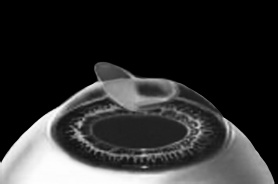

ЛАСИК – основной метод лазерной коррекции в мире в настоящее время. По большому счету, ФРК и ЛАСИК – единственные методы коррекции. Остальные методы являются либо модификациями ФРК и ЛАСИК, либо «компромиссом» между ними. Эпителий роговицы не трогают, так как он – залог быстрого заживления. Накладывают на глаз вакуумное кольцо – стальную присоску кольцевидной формы с присоединенной к нему трубочкой. Через трубочку из присоски отсасывается воздух, чтобы создать относительный вакуум. Отсасывает воздух главный аппарат для проведения ЛАСИКа – микрокератом. Это прибор размером с коробку из-под обуви. Его предназначение – срезание поверхностной крышки роговицы. К глазу присоединяют вакуумное кольцо, окружающее роговицу. Глаз четко фиксируется относительно кольца и сдвинуться с места может только с кольцом, в отверстие которого выступает купол роговицы. Затем к кольцу присоединяется головка микрокератома. Это второй инструмент микрокератома и соединяется с ним или шнуром, или тонким шлангом. Головка крепится на турбине, и вместе они имеют вид толстой шариковой ручки с обрубленным концом. Эту «ручку» хирург держит в правой руке, а вакуумное кольцо – в левой. Эта «ручка» нужна, чтобы сформировать крышечку роговицы. Внутри головки есть очень острое одноразовое лезвие. Турбина, соединенная с головкой, может двигать одноразовое лезвие туда-сюда, пилящими движениями. Можно резать роговицу, как хлеб, – пилящими движениями. И тут самое главное – скорость. Одноразовое лезвие делает 15000 пилящих движений в минуту. При такой скорости назвать это срезанием роговицы уже трудно, скорее это отслаивание верхних слоев. ![]() Рис. 3. Схема формирования роговичного лоскута с помощью микрокератома. Иллюстрация с сайта Международного лазерного центра www.optics.ru Итак, головка присоединяется к вакуумному кольцу и по специальным полозьям двигается над куполом роговицы (рис. 3). Срез, или отслаивание (называйте, как хотите), проводится не полностью, у крышечки (роговичного лоскута) остается маленький участок на периферии, соединяющий ее с роговицей (рис. 4). ![]() Рис. 4. Роговичный лоскут сформирован. Иллюстрация с сайта Международного лазерного центра www.optics.ru После формирования роговичного лоскута убирают инструменты микрокератома, затем шпателем откидывают его вбок (рис. 5). Обнажается роговичное ложе, то есть место, на котором лежал лоскут. Это верхние слои стромы роговицы. Ложе осушают тупфером и так же, как и при ФРК, настраивают лазер и испаряют несколько микрон вещества стромы (рис. 6). Потом промывают строму водой и шпателем укладывают лоскут на место. ![]() Рис. 5. Роговичный лоскут откинут в сторону. Иллюстрация с сайта Международного лазерного центра www.optics.ru ![]() Рис. 6. Луч эксимерного лазера испаряет на роговичном ложе несколько микрон стромы роговицы. Иллюстрация с сайта Международного лазерного центра www.optics.ru Стоит один раз моргнуть и лоскут скомкается и зрения не будет. Его бы пришить на место. Но швы деформируют роговицу. Все проще. Лоскут разглаживают мокрым тупфером, прижимая его ровненько к старому месту (рис. 7 и 8). Только место не старое, с роговичного ложа удалили несколько микрон в виде причудливой ямки (при коррекции близорукости). ![]() Рис. 7. При коррекции близорукости на роговичном ложе формируется «ямка». Иллюстрация с сайта Международного лазерного центра www.optics.ru ![]() Рис. 8. Роговичный лоскут укладывается на место. Иллюстрация с сайта Международного лазерного центра www.optics.ru Края роговичного лоскута осушают сухим тупфером. Влага, оставшаяся под лоскутом в ямке роговичного ложа, высасывается в тупфер. Лоскут притягивает к ложу, как вакуумную присоску. Вакуумом начали, вакуумом закончили. Ждем, когда закончится приживление лоскута к ложу. Эпителий цел и невредим. А значит, никаких болей. Около трех часов возможны слезотечение и светобоязнь. И все (рис. 9). ![]() Рис. 9. Форма роговицы до проведения коррекции (а) и после коррекции близорукости (б). Испарение нескольких микрон толщины роговицы привело к уменьшению ее кривизны в центре. Иллюстрация с сайта Международного лазерного центра www.optics.ru Хирурги о ЛАСИКе говорят: «90 % хирургии и 10 % долечивания». Лазерный субэпителиальный кератомилез (LASEK) Модификация ФРК. Чтобы укоротить неприятный послеоперационный период, эпителий, обработанный спиртовым или солевым раствором, отслаивают очень бережно, с помощью специальных инструментов, в виде цельного лоскута. А после испарения эксимерным лазером боуменовой мембраны и нужного количества слоев стромы этот эпителиальный лоскут укладывают обратно и, чтобы он не сместился, прижимают мягкой контактной линзой. Через 3–4 дня эпителий заживает, а благодаря линзе и даже еще не приживленному эпителиальному лоскуту боль и светобоязнь не беспокоят пациента с первых часов после коррекции, а зрение восстанавливается на пару недель быстрее, чем при ФРК. Также одной из модификаций ФРК является MAGEK. Основным отличием от ФРК является применение препарата Митомицин С (Mitomycin-С), который блокирует «слишком быстрое деление клеток» и снижает риск возникновения хейза. Эпи-ЛАСИК (Epi-LASIK) Нечто среднее между ЛАСИК и LASEK. Для отделения эпителия используются не спиртовой или солевой растворы, а специальный аппарат, очень похожий на микрокератом. Аппарат называется эпикератомом. Он отслаивает эпителий вместе с частью боуменовой мембраны в виде лоскута, похожего на лоскут при ЛАСИКе, только гораздо тоньше. После проведения коррекции лоскут также прижимают контактной линзой. Но не поврежденный химическим ожогом эпителиальный лоскут, да еще с остатками боуменовой мембраны, значительно сокращает период заживления и восстановления и снижает другие недостатки ФРК и LASEK, о которых будет сказано ниже. Рефракционный эксимерлазерный интростромальный кератомилез (РЭИК) |